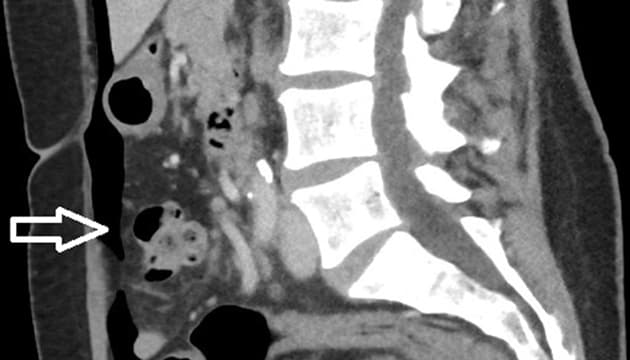

En 59-årig kvinde blev indlagt akut via kirurgisk akutmodtagelse pga. abdominalia. Hun var i 2007 blevet totalt hysterektomeret på benign indikation. Hun var normalvægtig, sund og rask og havde ikke tidligere fået foretaget abdominale indgreb. Hun havde et atypisk smertebillede i form af snigende smerter under højre kurvatur uden udstråling, som i løbet af et døgn flyttede sig ned til nedre abdomen. Hun fremstod ikke akut påvirket, men var lokalt peritoneal suprapubisk. Hun var afebril, havde normalt leukocytniveau og CRP-koncentration på 189 mg/l. Grundet det ikke helt entydige symptombillede overvejede man appendicitis, kolecystitis og ileus som tentative diagnoser. Patienten fik ikke foretaget en gynækologisk undersøgelse. Der blev udført en akut CT af abdomen. CT’en viste fri luft beliggende overvejende op mod forreste bugvæg (Figur 1). Grundet inflammatorisk reaktion omkring tyndtarmssegmenter fik man mistanke om perforeret tyndtarmsdivertikel, hvorfor der blev foretaget eksplorativ laparotomi. Her fandt man komplet ruptur af vaginaltoppen og let peritonitis uden absces lokalt over vaginaltoppen. Den gynækologiske bagvagt blev tilkaldt, og sammen lukkede man vaginaltoppen nedefra i to lag og lukkede abdomen. Ved efterfølgende gennemgang af skanningen så man små luftbobler i vagina og over vaginaltoppen (Figur 1).